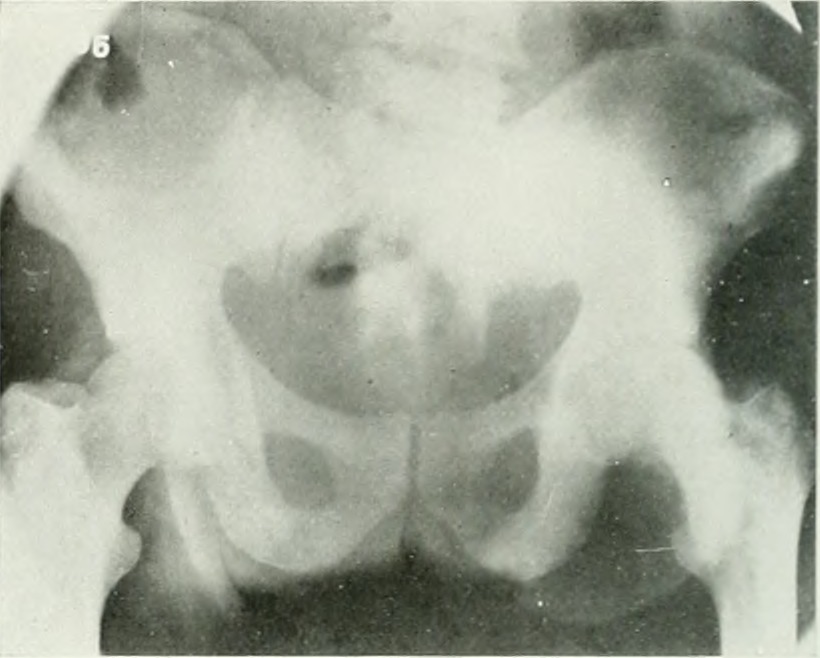

An X-ray of the pelvis in a patient with prostate cancer. Source: University of Toronto.

There’s no algorithmic calculation for prostate cancer treatment, but the complementary gesture is delayed screening—owed, perhaps, to black men’s ignorance about, inability to afford and barriers to, apathy against, or anxiety toward actively seeking or receiving preventative care. Prostate cancer is diagnosed through a rectal exam or a prostate-specific androgen (PSA) test; while testing healthy cisgender men without symptoms may be controversial, semi-regular testing for men over the age of fifty is a norm. Testing for black men is even more urgent because of increased risk factors: black men often develop the cancer at a younger age, and often in a more aggressive form than white men. My daddy is comically hypervigilant about medical screenings; his previous nonwhite doctor was adamant about regular PSA tests, but his new white physician was not. Daddy insisted on a blood test and was found to have massively elevated PSA levels, which indicate prostate cancer. I don’t want to think about what would have happened to him if he hadn’t insisted, but medicine’s discriminatory disregard toward black vigilance (often written off as needless paranoia) and the resultant delay in routine medical examinations has an influence on their mortality outcomes because of the seriousness of an illness at the eventual time of its detection.